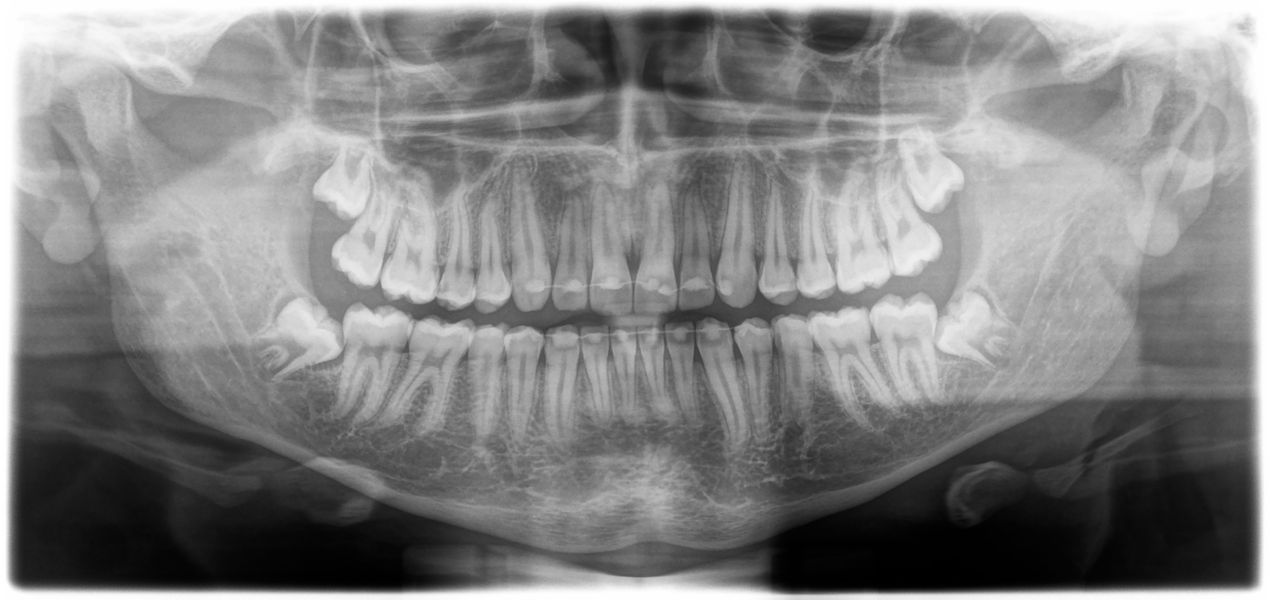

Panoramic Radiographic data acquisition is critical for optimum diagnosis and treatment planning as well as sequencing therapy. The course will review the foundation for systematic evaluation of panoramic images. In addition, the course will discuss the normal anatomic landmarks as well common abnormalities seen in panoramic radiographs.